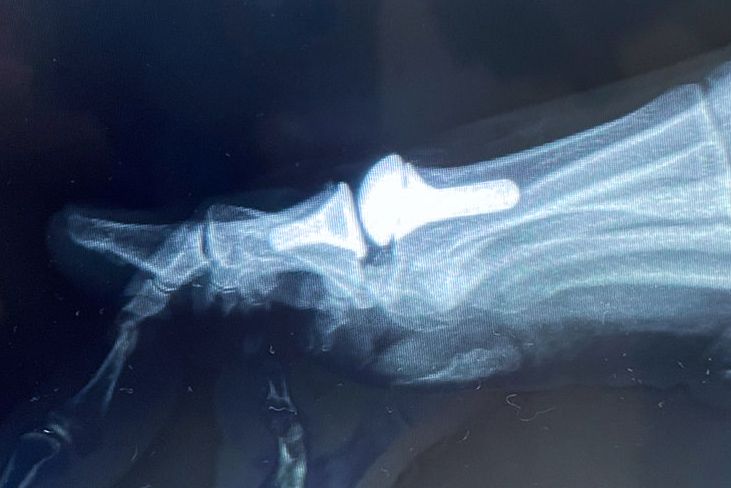

La fracturas en la mano deben ser tratadas por manos expertas, puesto que, un mal manejo tendrá siempre consecuencias catastróficas. La mano, para ser funcional, debe ser fuerte, estable, móvil, sensible, no dolorosa y estéticamente bella. Una mano que no cumpla con estas caracteristicas simplemente será inservible en mayor o menor grado para el paciente. Nuestra formación y experiencia nos permite realizar diagnósticos y tratamientos adecuados a cada paciente con el fin de que pueda recuperar su calidad de vida y función.